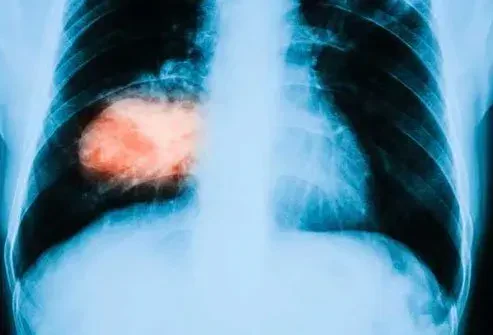

Cancer

Dans les études en laboratoire et animale, le curcuma a arrêté la croissance des cellules tumorales a aidé à détoxifier les enzymes mieux et plus encore. Ce que ces études ne peuvent pas nous dire, c'est ce qui se passera dans le corps humain lorsqu'une personne mange du curcuma. De plus, il y a une chance que le curcuma puisse interférer avec certains médicaments de chimiothérapie.